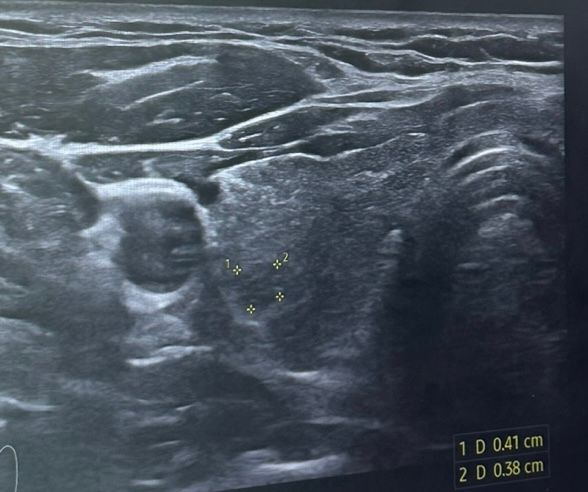

갑상선암 인가요? 의사쌤이 모양이 않좋다 하셔서

오늘 초음파를 받았는데 이게 종양이라 하시네요 아무리 봐도 저 점을 연결해봐도 안보이는데ㅠ 되게 안좋은 모양일까요…… 확인 부탁드립니다

주변보다 음영이 떨어져 보이는 결절이 보이고 있습니다.

이를 초음파 용어로 hypoecoic 하다고 판단하고 낮은음영의 결절은 단계가 올라가는 것으로 되어있기는 합니다. 크기는 작은편입니다.

그외에는 악성이 의심되는 suspiciois feature 는 없기에 KTIRAD 단계로 따져본다면 solid hypoechoic nodule, 4단계로 보입니다. 1cm 이상이면 FNA 정밀검사가 필요합니다. 전문의 상의하 추가 검사 혹은 주기적 추적검사를 결정하실수 있을 것으로 사료됩니다.